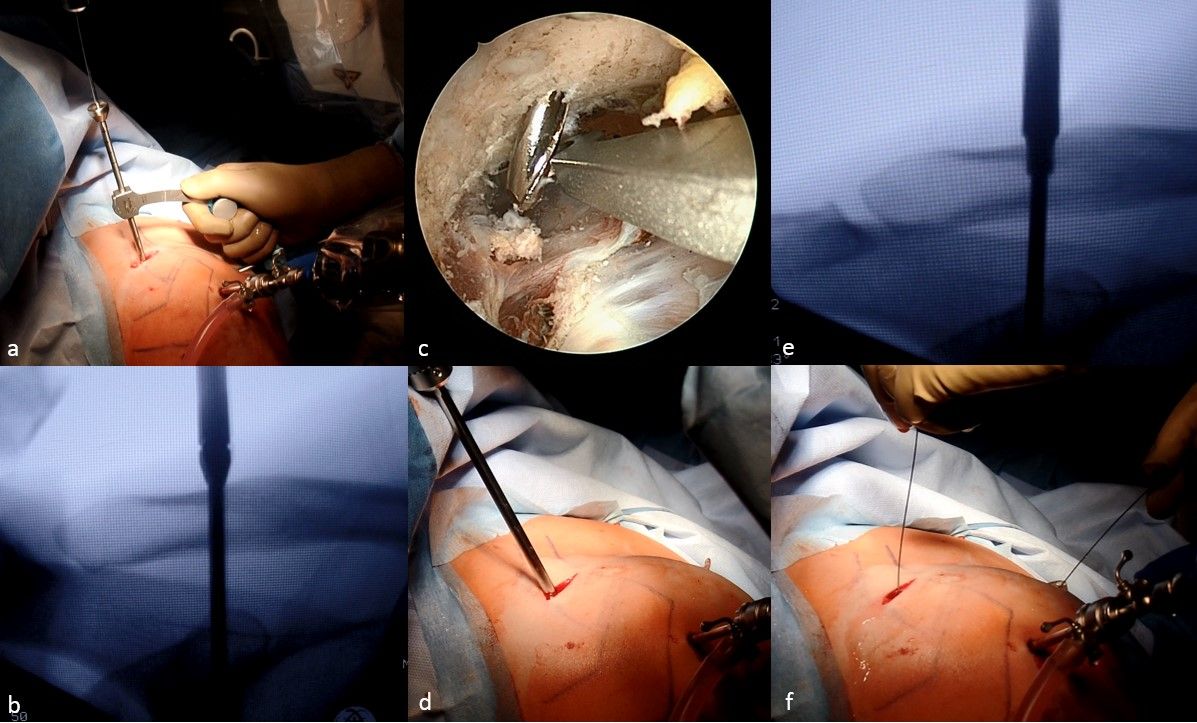

Coracoclavicular drilling

An image intensifier is used for the correct placement of the drill holes and the anatomical reduction of the AC joint. For coracoclavicular drilling an adjustable drill guide is used and the marking hook is introduced through the anteroinferior portal under direct visualization and placed under the central part of the coracoid base. The other end with the drill sleeve, is placed about 3cm medial from the lateral end of the clavicle. The drill hole is established in between the previous coracoclavicular ligaments in a transclavicular-transcoracoidal fashion. With the drill guide held in this position and under arthroscopic control, a 3mm drilling through the clavicle and the base of the coracoid is performed using a drill bit with an implemented K-wire (Fig 3a). Alternatively, a 2 mm K-wire can be used that is overdrilled using a 3.5 mm drill. The correct placement of the coracoclavicular drilling is controlled using the image-intensifier (Fig 3b & c).

Subsequently the drill is unicortical overdrilled using a 5.1 mm drill bit (Fig 3d & e). The K-wire is then removed and a nitinol suture passing wire is inserted via the cannulated drill bit into the subcoracoid space and retrieved via the anteroinferior portal (Fig. 3f). The cannulated drill bit can then be removed.